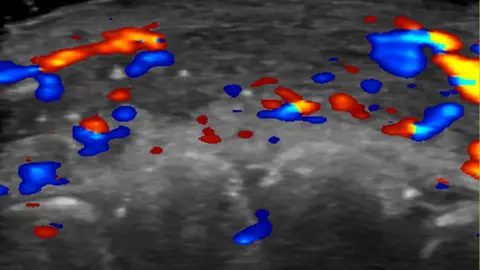

An ultrasound scan of a patient's lip shows absent blood flow (black areas located at the top, middle of the picture) in a segment of an artery. Meanwhile, red shows blood flow towards the ultrasound probe, while blue shows flow away from it.

In just under half the cases, ultrasound scans showed absent blood flow to small blood vessels that connect superficial arteries to deep ones in the face.

And in a third of cases, blood flow was absent in major blood vessels.